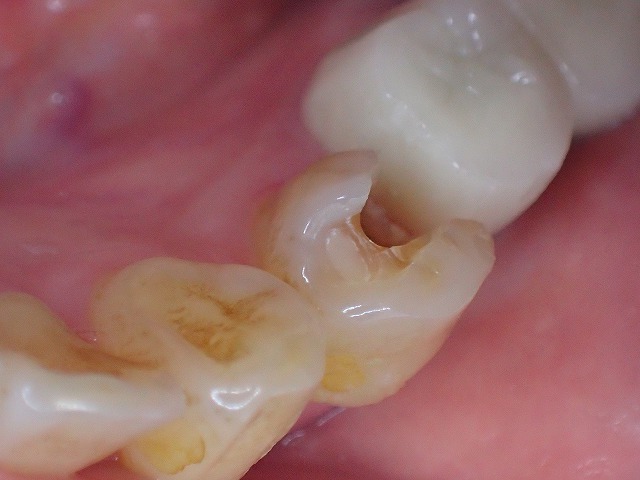

ジルコニアのインレーは適合悪いでおすすめできません。

ジルコニアではんく インレーはe.maxセラミックがおすすめ